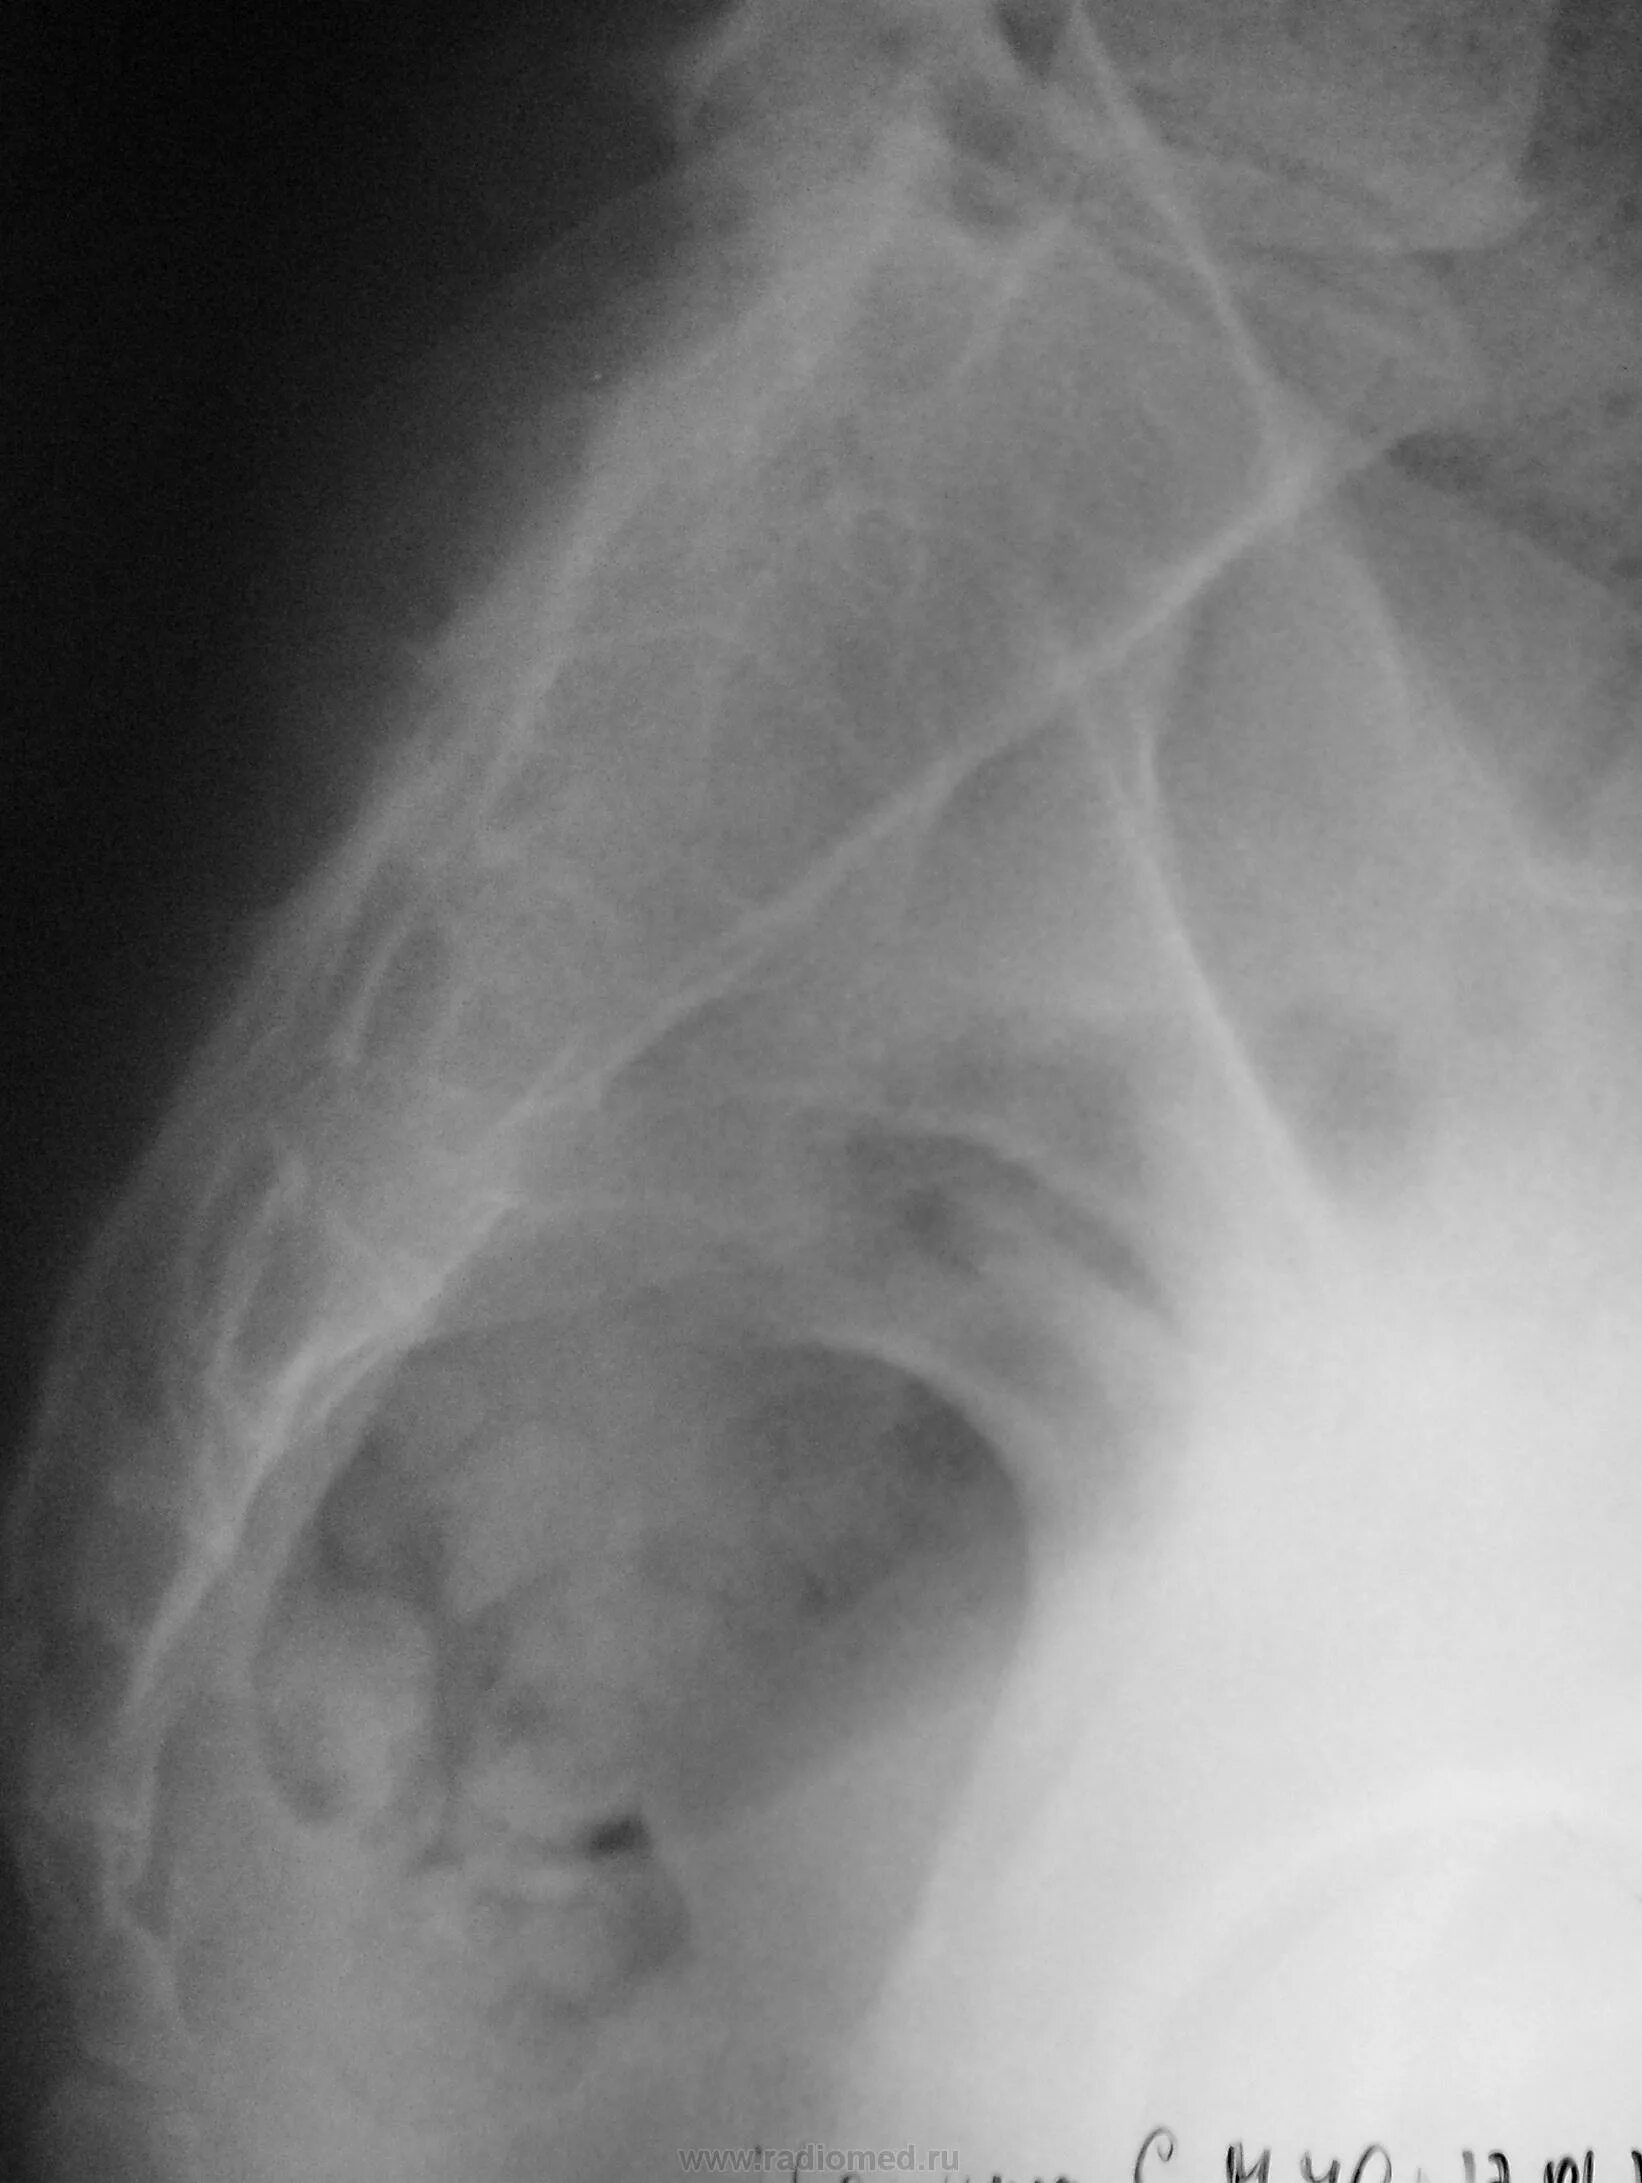

Снимок копчика